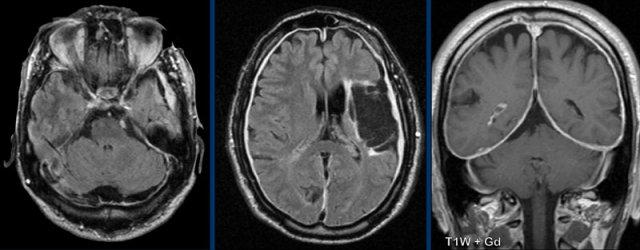

Các hình ảnh này của một phụ nữ 76 tuổi, có biểu hiện lú lẫn sau khi ngã.

Các dấu hiệu bao gồm:

- Tổn thương tăng tỷ trọng trên CT không tiêm thuốc cản quang kèm phù não do mạch máu.

- MRI cho thấy nhiều tổn thương ngấm thuốc dạng đặc và hạn chế khuếch tán.

- Trên chuỗi xung T2W, các tổn thương biểu hiện giảm tín hiệu.

- Một tổn thương nằm ở thể chai và một tổn thương khác nằm cạnh não thất.

Tất cả các dấu hiệu này đều điển hình cho u lympho nguyên phát hệ thần kinh trung ương, khác với u lympho hệ thống.

Các khối u này chiếm 6-7% tổng số u hệ thần kinh trung ương và mô học là u lympho tế bào B không Hodgkin.

Chúng thường nằm ở vùng cạnh não thất dưới màng nội tủy, thể chai và hạch nền.

Luôn nghĩ đến u lympho khi gặp tổn thương ngấm thuốc dạng đặc nằm gần não thất.

Hình ảnh tăng tỷ trọng trên CT, giảm tín hiệu nhẹ trên chuỗi xung T2W cũng như hạn chế khuếch tán được giải thích là do mật độ tế bào dày đặc của mô u lympho.